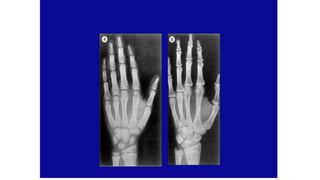

Bone Age

Dept of Pediatrics, AFMC 43

• What are the radiographs that you will prefer to assess bone age at

- < 1 yr

- 1 – 12 yrs

- > 12 yrs

Bone Age Estimation

• X-Ray left hand with wrist

• Scoring system of each of 20 individual hand bones

(Tanner-Whitehouse Method, TW2), a technique that has

been adapted for computerized assessment

• BA is a better predictor pubertal milestones than CA